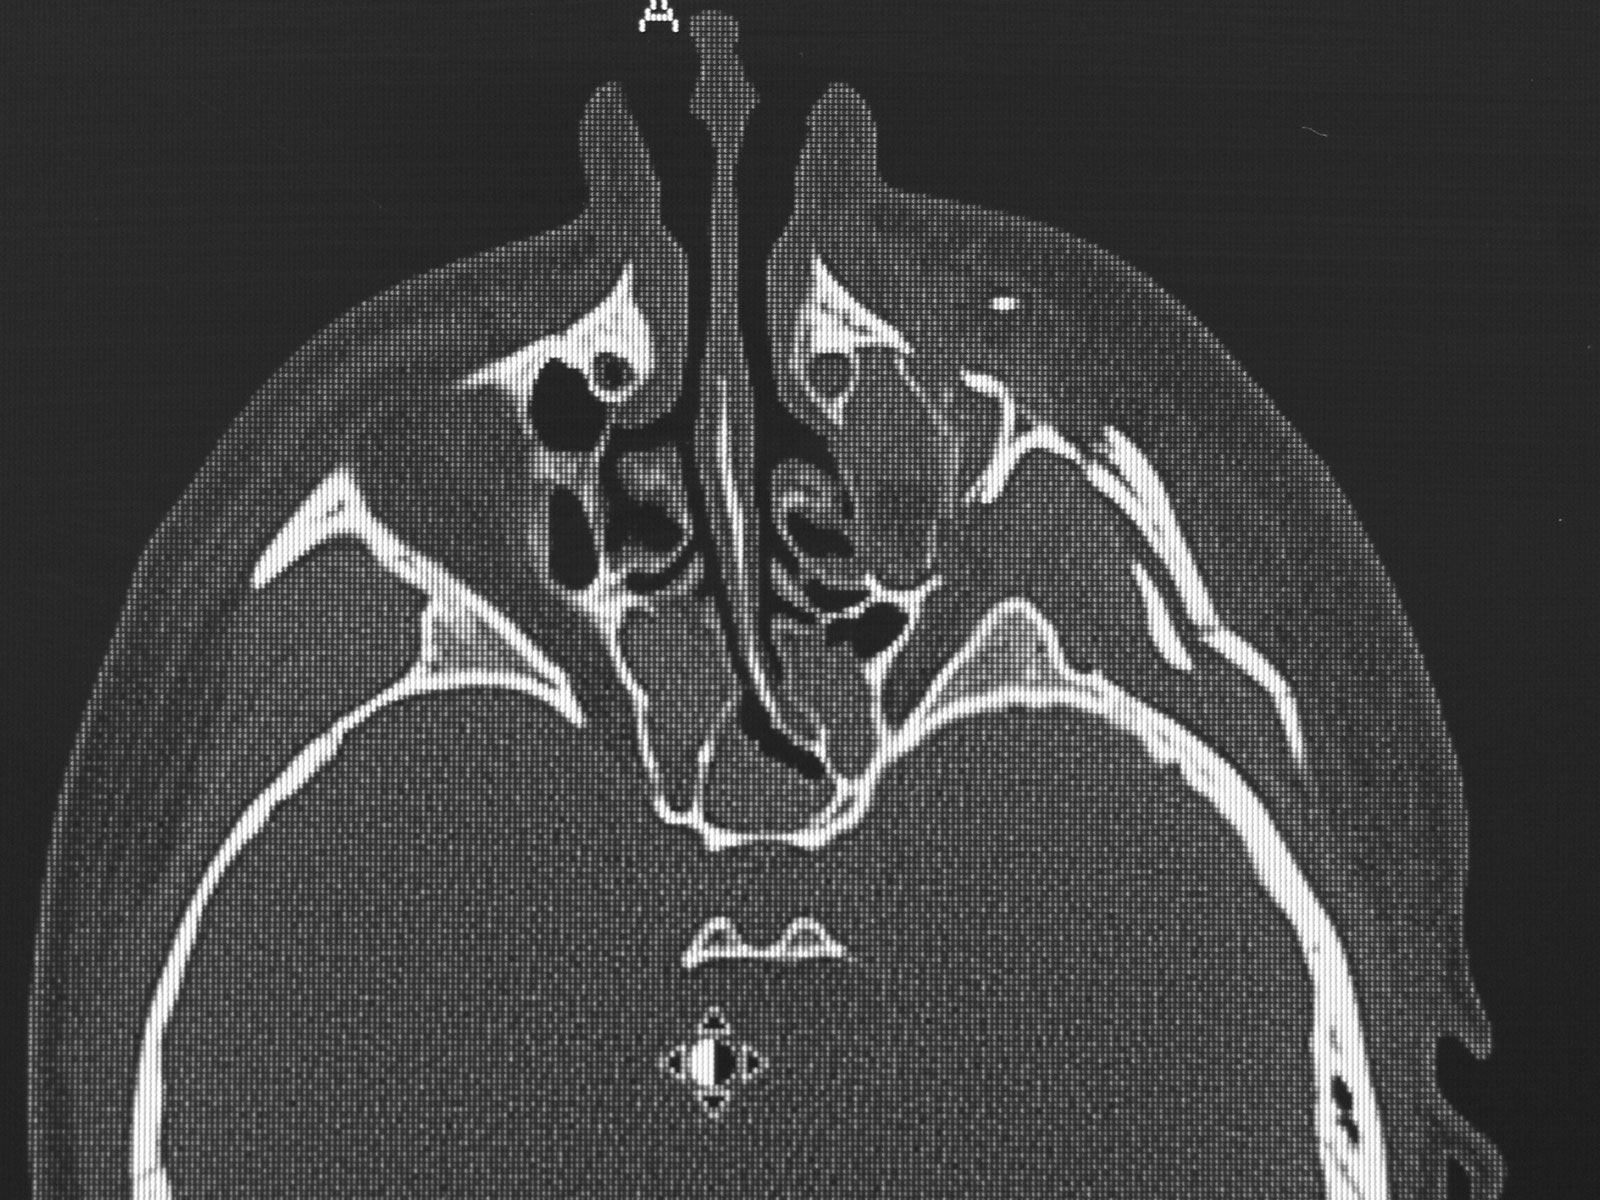

I underwent a number of procedures, the first occurring the day of my accident, to correct severe damage to my face. As Dr. Ulloa put it my face was, 'in a million pieces.  At one point there was even some bone that had lodged in my eye. He was able to address this and ended up saving my eyesight, along with reconstructing my facial features.

The photos on this website are from real surgeries performed by Dr. Ulloa. Due to the

graphic nature of the images and content, viewer discretion is advised.

Click to enlarge images